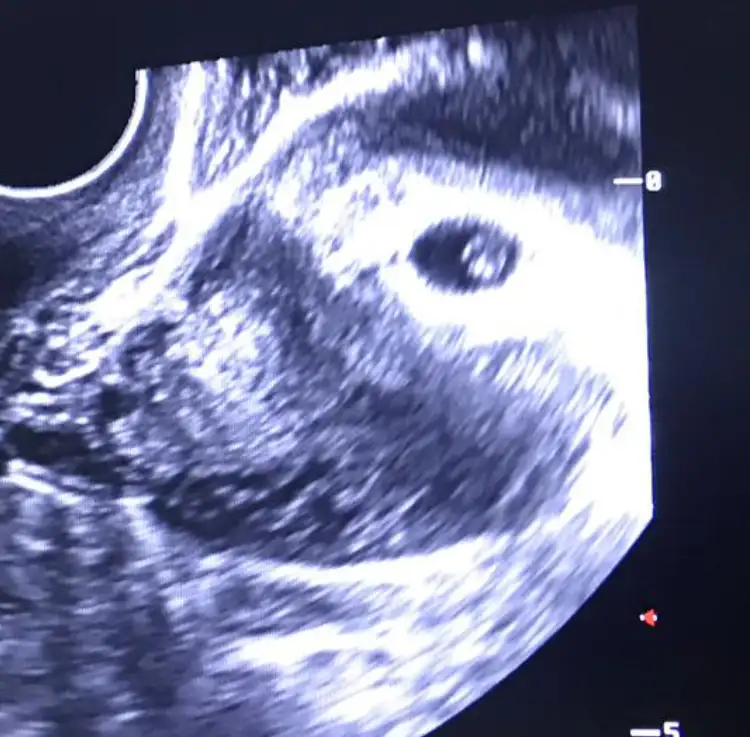

inanmıyorum. bize de söyle eski usülleri bende yapayım canım meraktan çatlıcam ne çıkacakKız istiyorum:))KEndımı bildim bileli kız istiyorum hatta o kadar kız olsun istiyorum ki cümlelerimi çok dikkatlı seçiyorumTabiili sağlıklı ve hayırlı bir birey olması önemli ama kız olsun.Eski usül ne kadar cinsiyet belirleme hesabı varsa yaptım,çin takvimide ilk ultrason görüntüsüde dahil